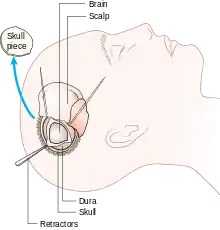

Diagram of the elements of a craniotomy.

Human craniotomy is usually performed under general anesthesia but can be also done with the patient awake using a local anaesthetic; the procedure, typically, does not involve significant discomfort for the patient. In general, a craniotomy will be preceded by an MRI scan which provides an image of the brain that the surgeon uses to plan the precise location for bone removal and the appropriate angle of access to the relevant brain areas. The amount of skull that needs to be removed depends on the type of surgery being performed. The bone flap is mostly removed with the help of a cranial drill and a craniotome, then replaced using titanium plates and screws or another form of fixation (wire, suture, etc.) after completion of the surgical procedure. In the event the host bone does not accept its replacement, an artificial piece of skull, often made of PEEK, is substituted. (The PEEK appliance is routinely modeled by a CNC machine capable of accepting a high resolution MRI computer file in order to provide a very close fit, in an effort to minimize fitment issues, and therefore minimizing the duration of the cranial surgery.)